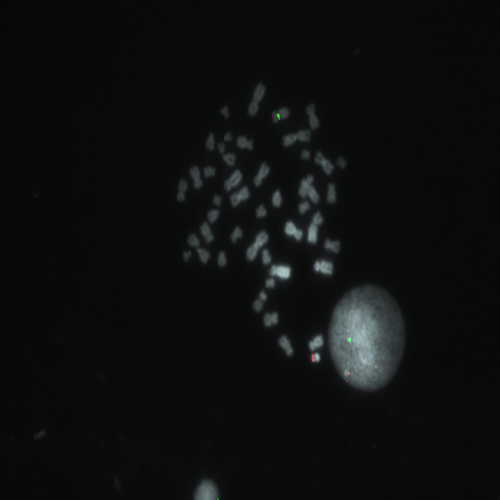

Hybridization of SE X / SE Y probe to a male metaphase spread showing normal pattern (1R1G).

IVD SE X/SE Y

Chromosomal abnormalities involving the X and Y chromosome (sex chromosomes) are slightly less common than autosomal abnormalities and are usually much less severe in their effects. The high frequency of people with sex chromosome aberrations is partly due to the fact that they are rarely lethal conditions. - Turner syndrome occurs when females inherit only one X chromosome - their genotype is X0. - Metafemales or triple-X females, inherit three X chromosomes - their genotype is XXX or more rarely XXXX or XXXXX. - Klinefelter syndrome males inherit one or more extra X chromosomes - their genotype is XXY or more rarely XXXY, XXXXY, or XY/XXY mosaic.